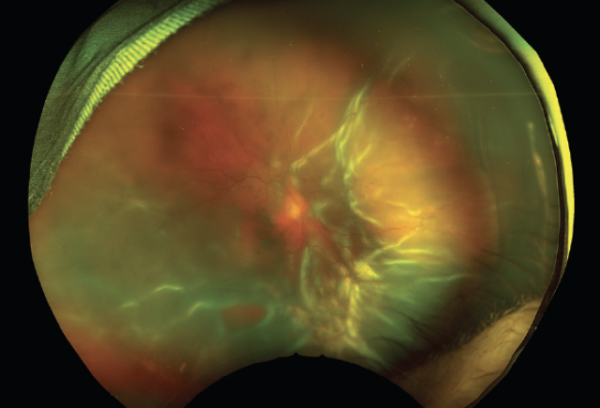

圖1. 這是一位87歲男性的眼底照片,患有多種合併症

與年輕成人患者(40到79歲)相比,老年患者(80歲及以上)更容易出現視網膜黃斑脫離(49%vs66%,PP=0.023)。此外,59%的老年患者的VA低於20/200,而且老年患者的平均VA低於年輕組(20/500vs20/200,P

在對老年患者進行手術之前,外科醫生必須仔細考慮將要使用的麻醉型別。雖然全身麻醉會增加合併症的風險,但在某些情況下可能是必要的,如無法保持靜止或保持正確體位的患者、有身體殘疾或認知困難的患者。在研究佇列的患者中,大多數採用監護麻醉護理和局麻,而不是全麻。大多數老年患者是人工晶狀體眼(90%vs 44%【年輕患者】,P

術後定位是視網膜脫離修復成功的關鍵。然而術後定位,可能不適用於伴有肌肉骨骼疾病的老年患者。在系列研究中,老年患者使用矽油的增加反映了RRD的複雜性和術後定位的潛在困難。研究人員發現,儘管更多的RRD老年患者接受PPV治療,但接受SB+PPV的患者單次手術成功率更高(SB+PPV組為91%,單獨PPV組為74%,P=0.03)。由於大多數老年患者都做過白內障手術,外科醫生通常傾向於僅用PPV治療假性RRD,以防止近視漂移和其他潛在的SB相關問題。雖然大多數患者單獨使用PPV有良好的結果,但在一些患者中增加SB可能是有益的。術中,醫生應小心操作眼外肌,因為眼心反射可導致心律失常,這對已有心臟合併症的老年患者尤其危險。此外,由於老年患者更容易出現骨關節炎和神經痛,因此外科醫生應儘可能避免長時間的手術。